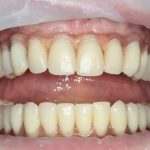

Рекомендации по установке имплантов. Для всех. Часть V.